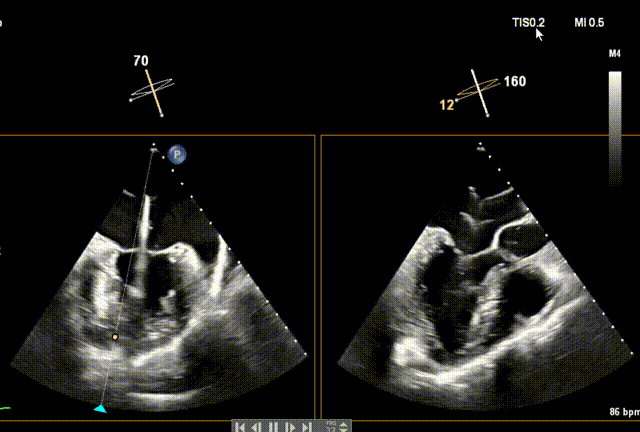

术前经食道超声(TEE)评估

术前TEE

DMR P2脱垂连枷(脱垂范围:12mm,连枷间距:3mm),反流2区,MR重度(VC:4* 10mm),A2:21mm,P2:10mm,AP:30mm,MVA约 4.7 cm²。